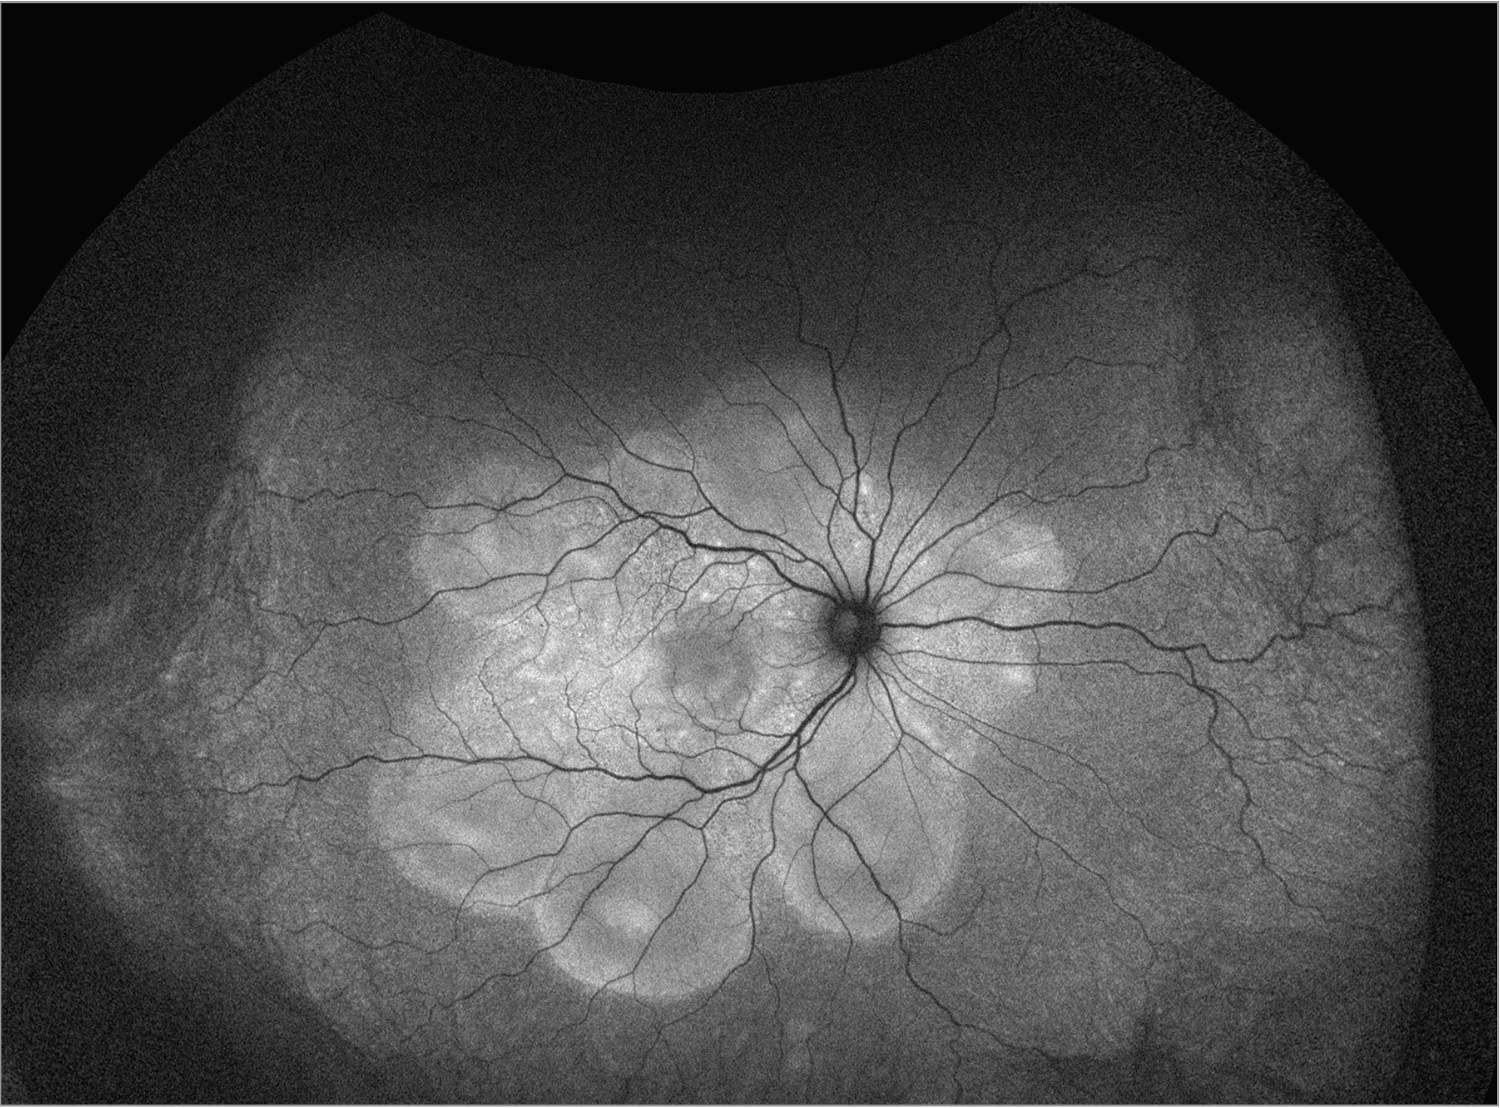

| Figure 1. Pseudo color fundus photo of the right eye with 360 degrees of serous choroidal detachments, bacillary detachments, and exudative subretinal fluid. |

Fundoscopic examination of both eyes demonstrated normal optic discs and normal vasculature; however, there were 360 degrees of serous choroidal detachments and large pockets of subretinal fluid throughout the macula and mid-periphery (Figures 1, 2). Fundus autofluorescence demonstrated hyperautofluorescence within the pockets of subretinal fluid in the macula and mid-periphery of both eyes (Figure 3). Fluorescein angiography revealed diffuse leakage of the peripheral vessels in both eyes and pooling corresponding to the pockets of subretinal fluid in both eyes. There were pinpoint areas of hyperfluorescence, most notable in the left eye, reminiscent of a “starry sky” appearance (Figure 4). Indocyanine green angiography revealed mixed hyper- and hypofluorescence of the macula. Optical coherence tomography of both eyes demonstrated multiple areas of large bacillary detachments in both eyes (Figures 5, 6).